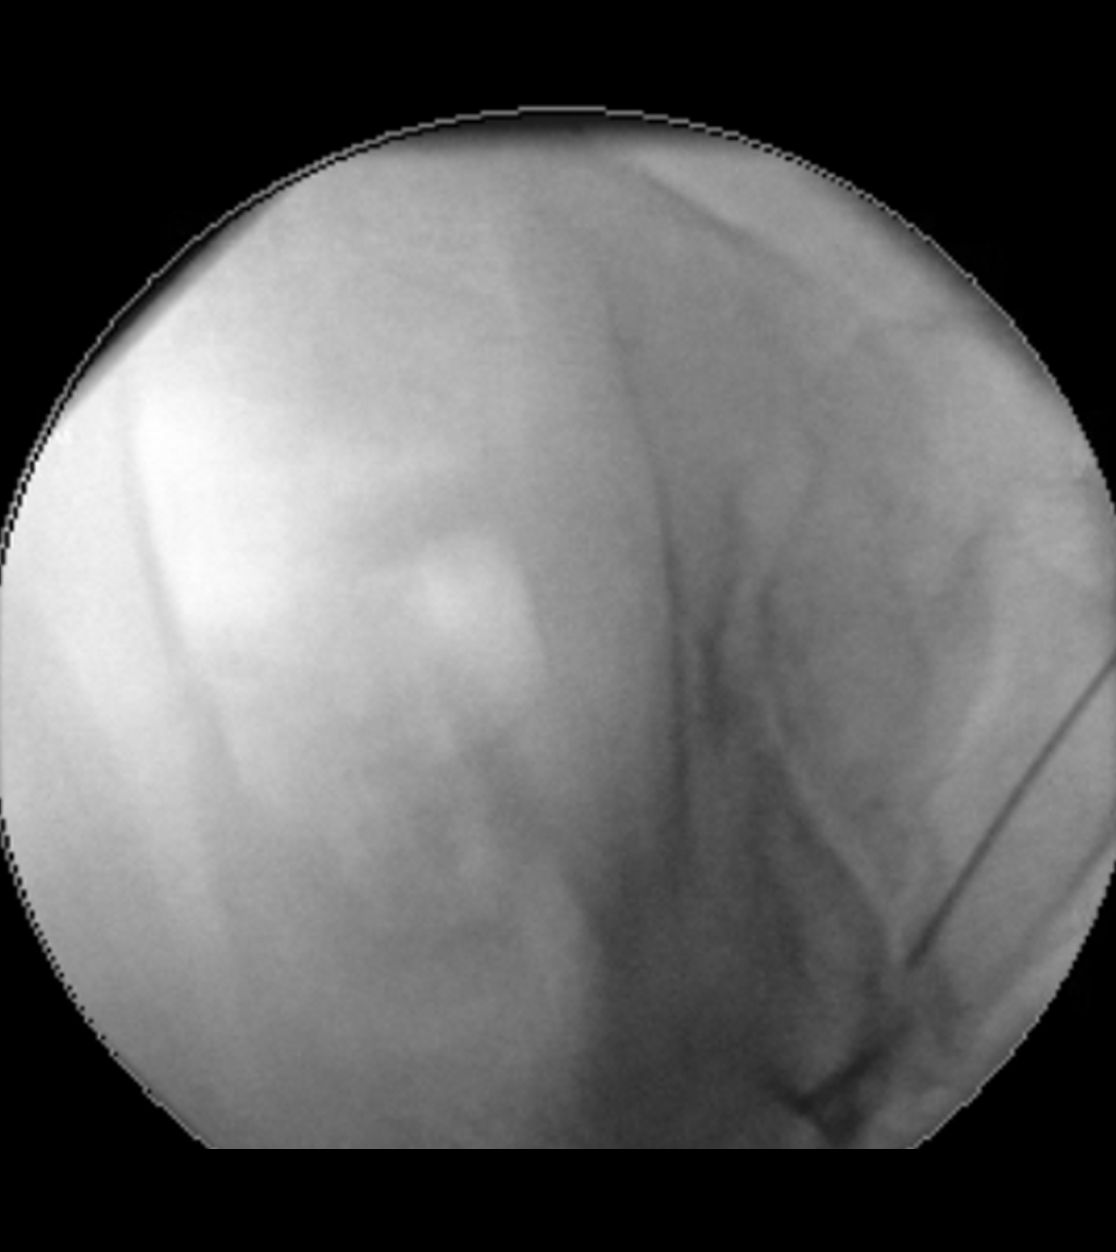

Im Nervenwasserraum (Liquor) einliegender Schlauch zur intrathekalen Therapie (Pfeil)